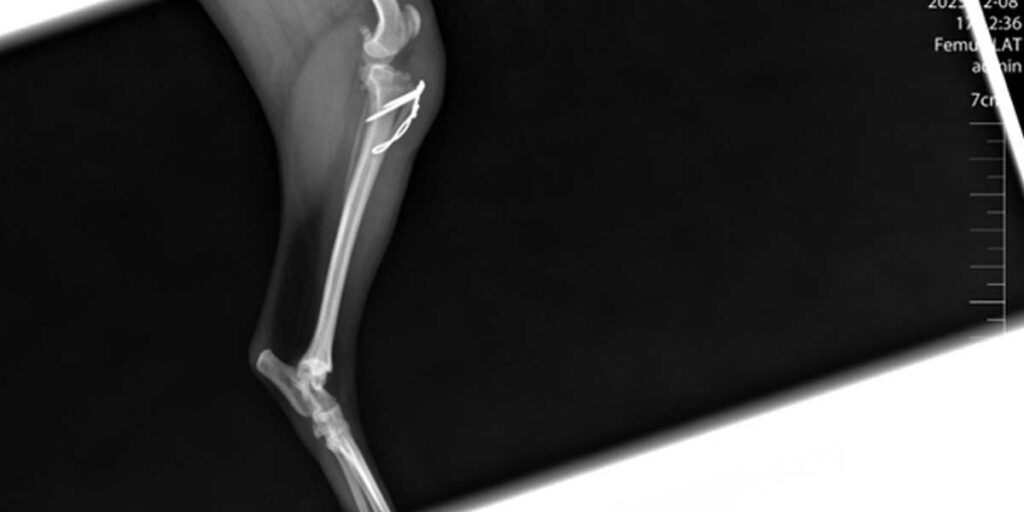

Liječenje može biti konzervativno, pomoću gipsa ili udlage, ili kirurško, uključujući pločice, vijke, čavle ili vanjsku fiksaciju.

Kirurško liječenje omogućuje precizno poravnanje kostiju i stabilnost tijekom cijeljenja, što skraćuje vrijeme oporavka.

Nakon operacije potrebna je stroga kontrola kretanja i povremene kontrole kod veterinara kako bi se pratilo pravilno cijeljenje.